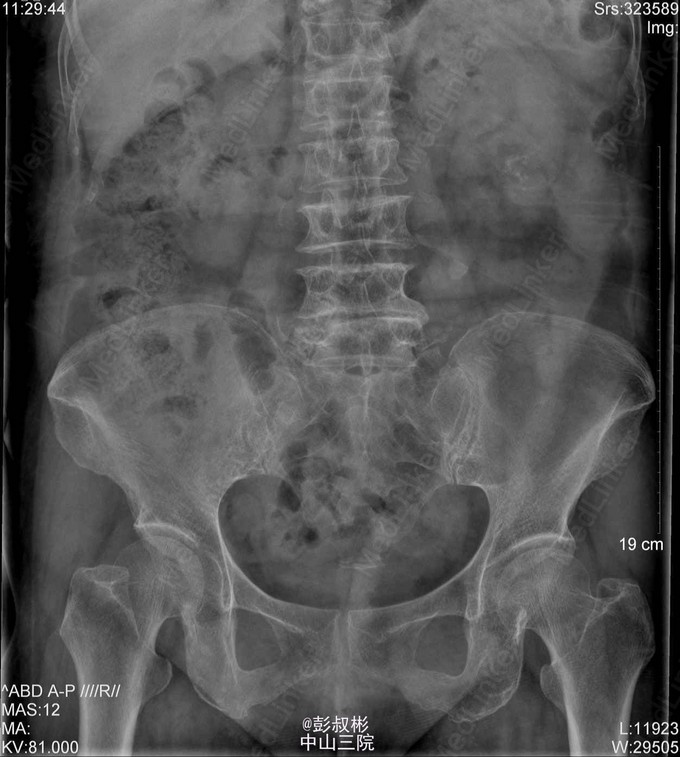

1、患者,女 80岁 2、主诉:左侧腰痛伴发热2天。 3、病史:患者于2天前无明显诱因突发左侧腰痛伴发热,畏寒,最高体温40.1℃,经急诊入院。患者曾于1年前被诊断为“双肾多发结石”,行“左侧经皮肾镜碎石取石术”后好转出院。 4、入院查体:左肾区叩击痛(+),左侧肋脊点、肋腰点压痛(+)。 5、辅助检查:KUB检查示:考虑左输尿管上段结石。B超提示:左肾积脓。胸部正位片:1、双肺纹理增粗,双下胸膜增厚。2、心影增大,主动脉硬化。 6、诊疗过程:患者于入院当晚突发高热、伴寒战、畏寒,最高体温40℃,伴恶心、呕吐,立即予抗感染等治疗。经有效治疗后患者体温有所下降。 随后患者突发抽搐,仍伴寒战、畏寒、意识模糊,予地塞米松10mg静推,加用凡拉蒙2ml肌注,非那根20mg肌注,冬眠灵12.5mg肌注后,控制仍不佳。遂行床边穿刺、抽脓。术后症状有所缓解。术后继续抗感染,患者体温恢复正常,症状明显缓解,无其他不适,遂予出院。